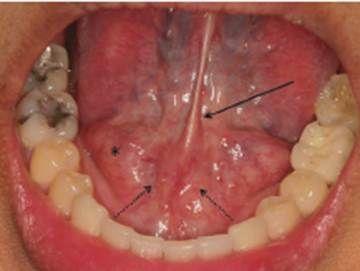

3.頜下間隙感染:智齒冠周炎或者下頜磨牙根尖周炎久治不愈,細(xì)菌通過頜下淋巴結(jié)擴(kuò)散到頜下三角,出現(xiàn)下頜部腫脹疼痛,舌下腫脹,也可出現(xiàn)張口困難,需要緊急進(jìn)行手術(shù)排膿引流。2.咀嚼肌下間隙感染:當(dāng)?shù)谌パ拦谥苎滓卜Q為智齒感染時(shí),如果沒有時(shí)間進(jìn)行治療的話,細(xì)菌容易擴(kuò)散到咀嚼肌下間隙,引起感染,可出現(xiàn)半個(gè)臉腫脹疼痛,也可出現(xiàn)張口困難,需要緊急手術(shù)排膿抗菌消炎處理,不然的話,有可能引起下頜骨骨髓炎。